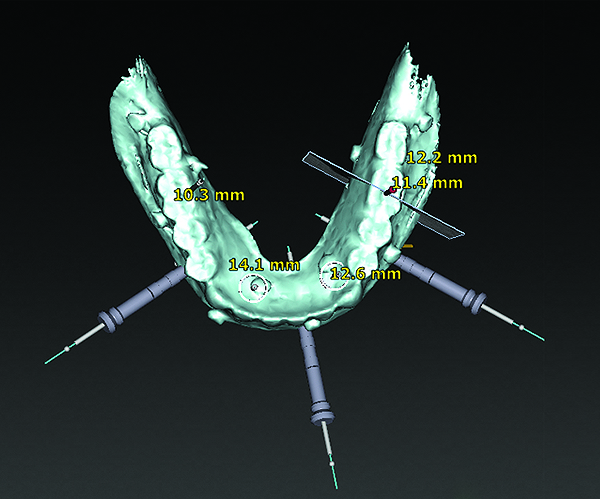

(12) An example of a surgical guide produced using digital design and digital planning of implant position using the double scan protocol.

Figure 12